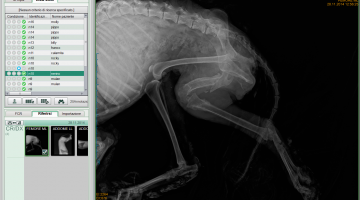

Macchinari digitali

Attualmente la nostra struttura è munita di un apparecchio radiologico digitale indiretto Fuji. (Nella photogallery in basso). I vantaggi di questa tecnologia rispetto alla radiologia “analogica “ tradizionale sono molteplici. Primo fra tutti la qualità dell’immagine e la possibilità di ingrandire i particolari, correggere i contrasti, visualizzarla in negativo, ma anche misurare con precisione i dettagli. Poi la notevole riduzione dei tempi dello studio radiografico che in campo veterinario significa anche la riduzione dei tempi di anestesia del paziente con beneficio per la sua salute. Le lastre digitali non inquinano l’ambiente. Sono dei files che possono essere trasmessi per posta elettronica, masterizzati su cd o pennette di memoria da mettere nella cartella clinica da consegnare al proprietario del paziente e, nel caso della nostra struttura allegati in rete e nella scheda clinica dell’animale.